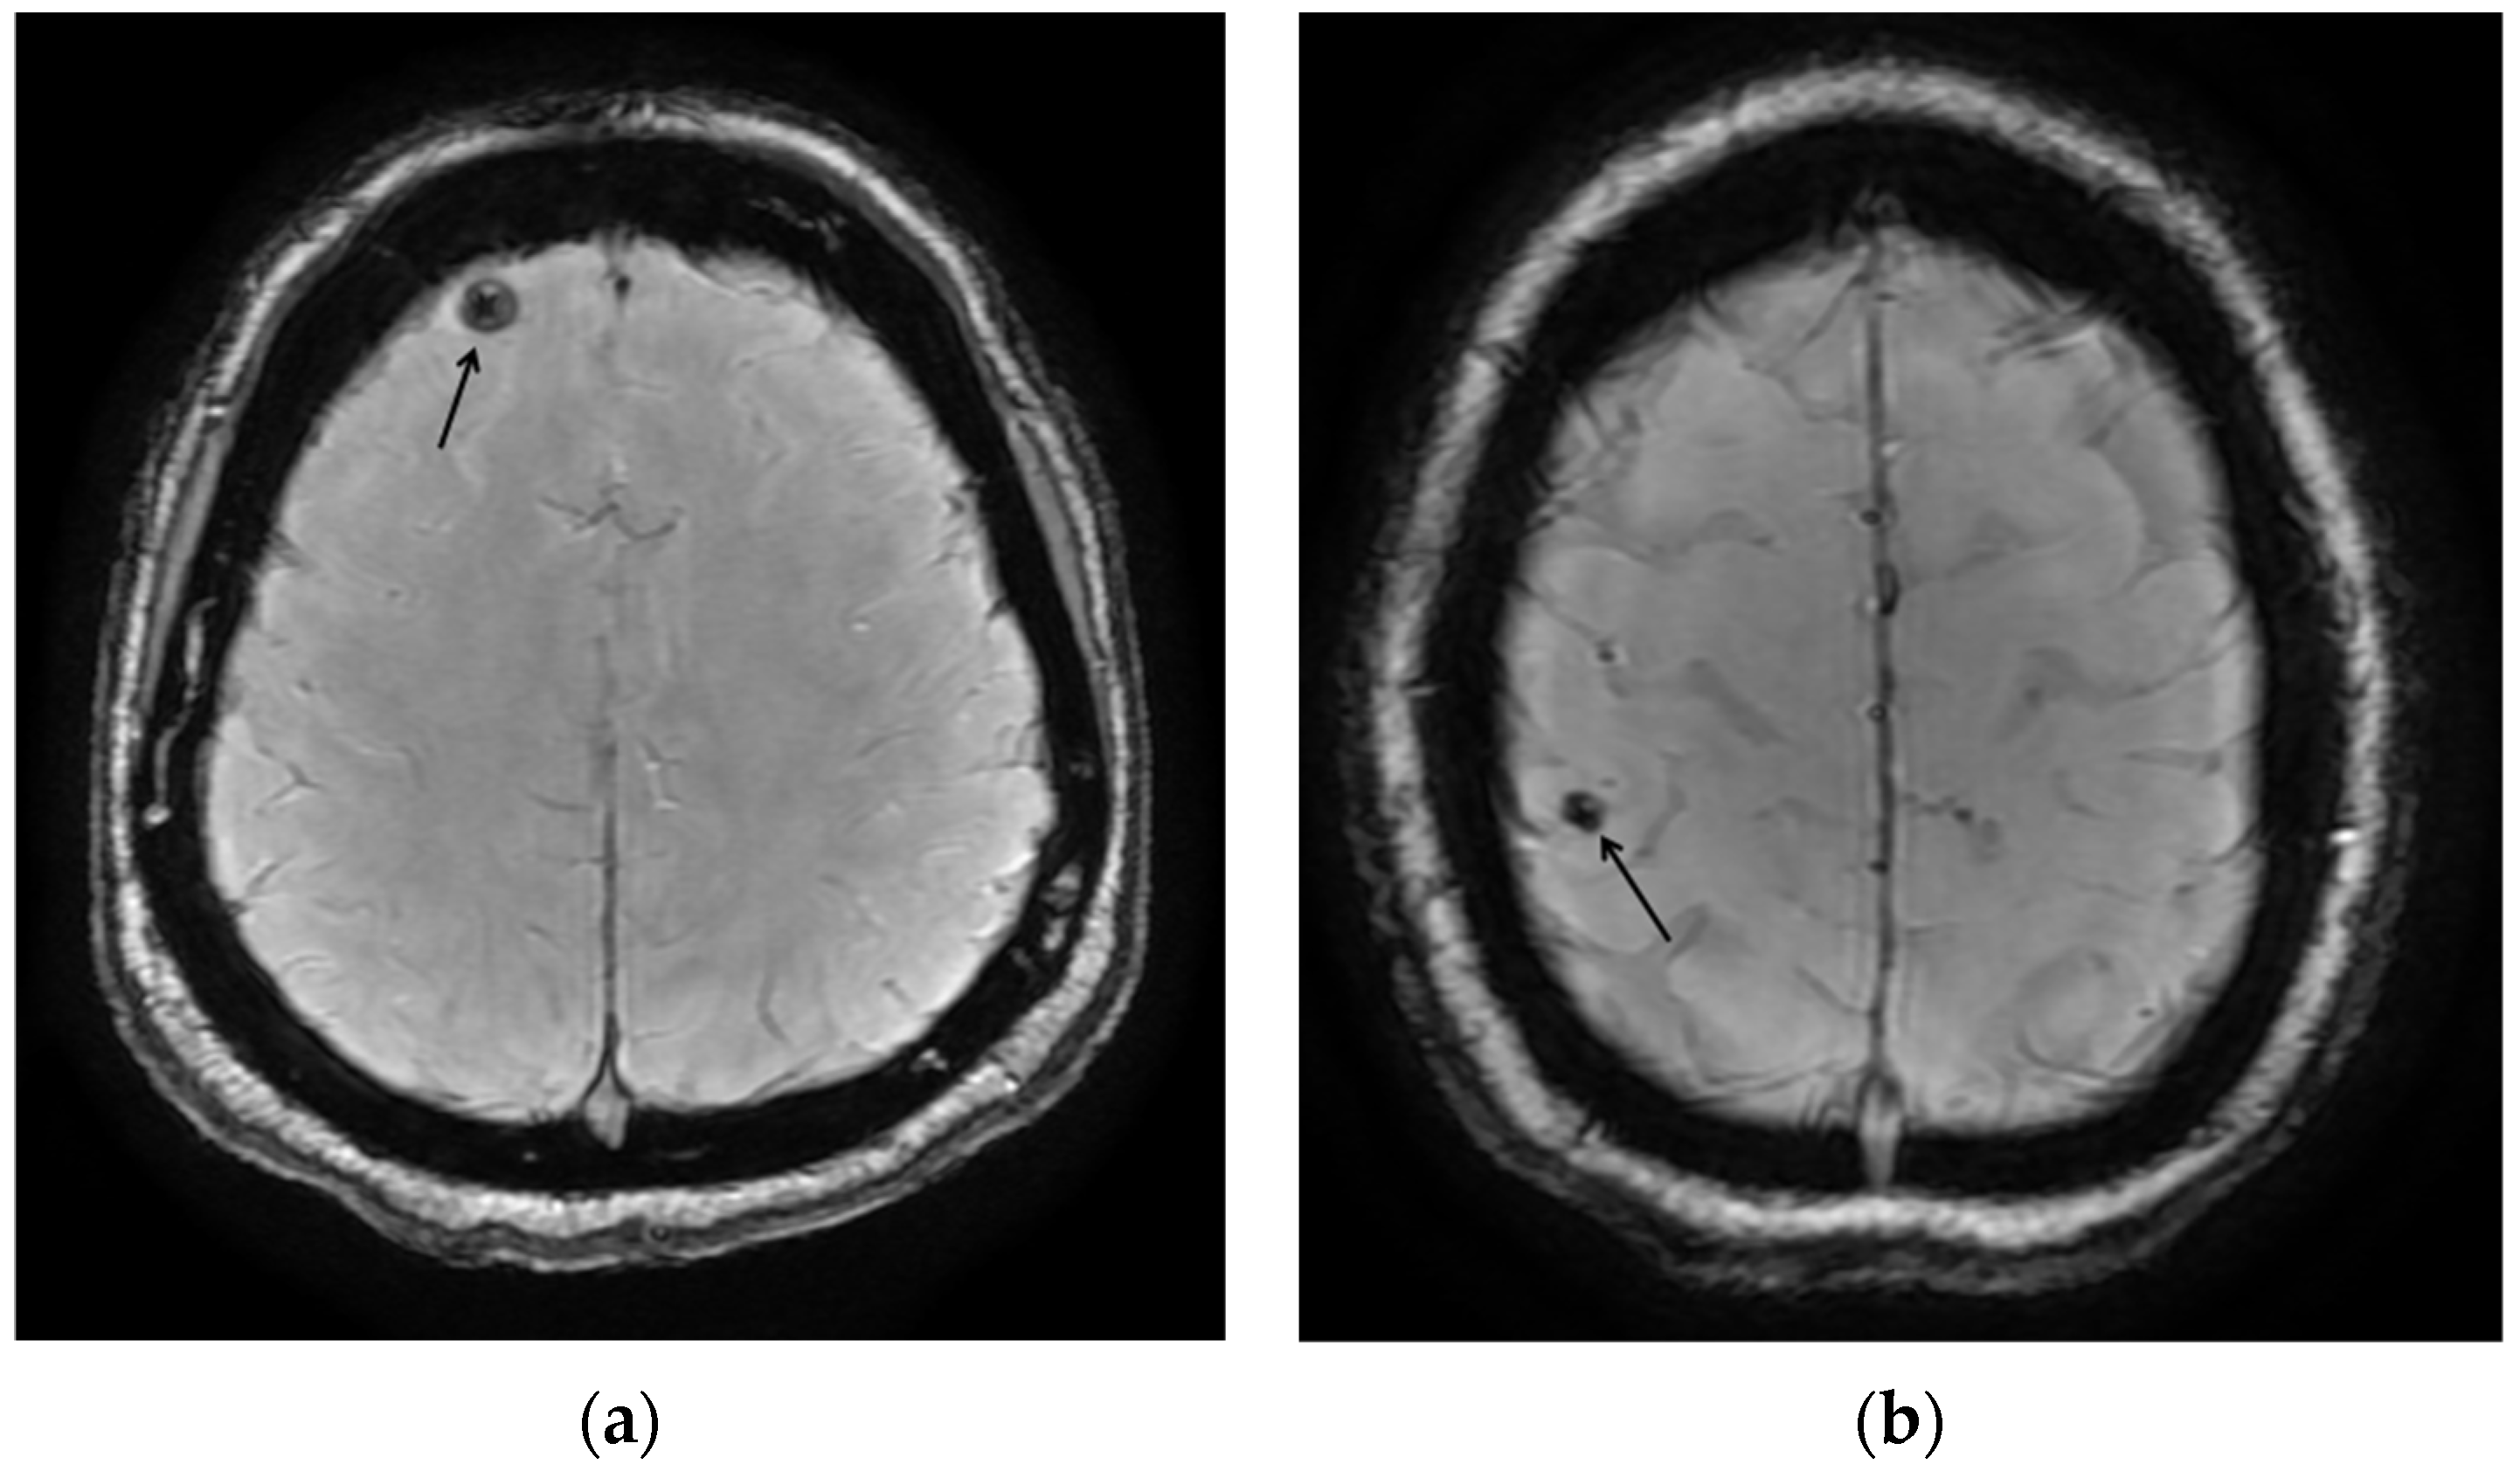

| NC0074 | Female | Yes | Mexico | 40–49 | Healthcare, caregiving, and social service | No | Yes | No | No | Positive |

| NC0126 | Female | No | Mexico | 40–59 | Healthcare, caregiving, and social service | No | Yes | No | No | Positive |